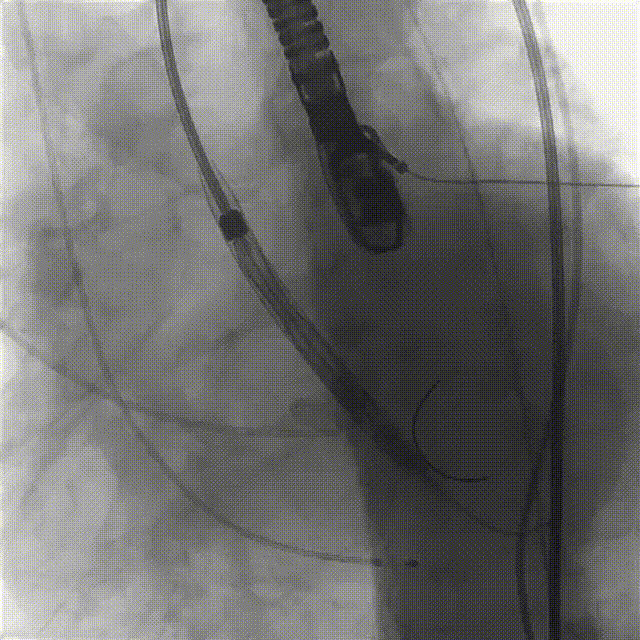

6.在150次/分快速起搏下释放瓣膜至工作位

7.瓣膜释放至工作位后造影示左右冠灌注尚可,瓣膜形态尚可,决定予以释放

8.造影见明显反流影,瓣膜受限明显,决定予以球囊后扩

9.150次/分快速起搏下以23mm 巴尔特球囊进行后扩张

10.猪尾导管测压显示,平均跨瓣压差约12mmHg,造影示瓣膜定位尚可、开放良好,少量瓣周漏,患者血流动力学指标稳定,血压约100/70mmHg,升主动脉未见造影剂潴留或渗漏,标志手术成功。

(2)由于患者升主动脉严重扩张,血管并发症风险较高,术中提前将抓捕器备于瓣膜输送系统上,直接于抓捕器辅助下送入瓣膜。得益于良好的控制,基本未使器械与扩张的血管壁接触,极大减少了血管并发症风险。